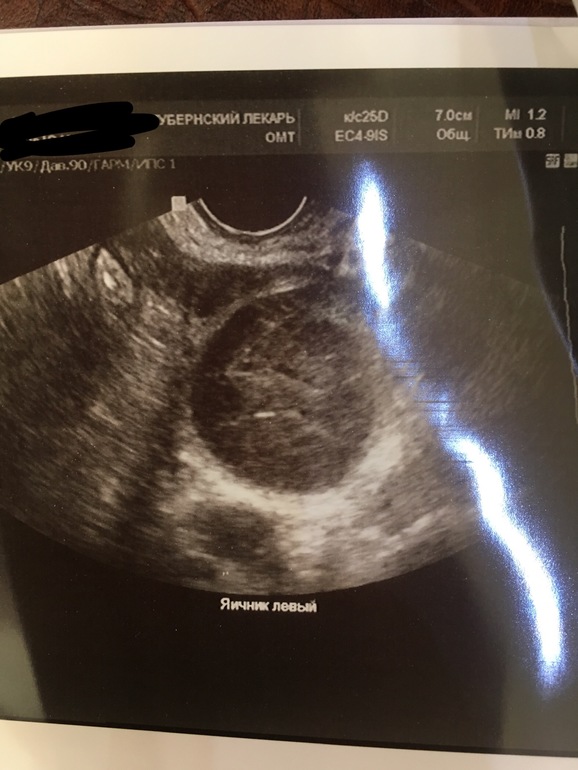

А это фолликулы ? На яичнике?

А кисту не на правом ставят? Просто тут, что-то не понятное. Мне показывали яичники, круглые, а тут не понятно

Жаль мне фото не дали, я бы показала, как у меня выглядели с фоликулами. Опишу так. Вот как у вас левый яичник, круглое пятно, а на нём тёмные маленькие пятнышко. Вот на них узистка и указала, что это фолликулы. Там их по 4 и 5 штук на каждом яичнике ну и один доминантный 20 мм был. Вот на него и думали, что это жт, но оказался фоликом

Это яичник